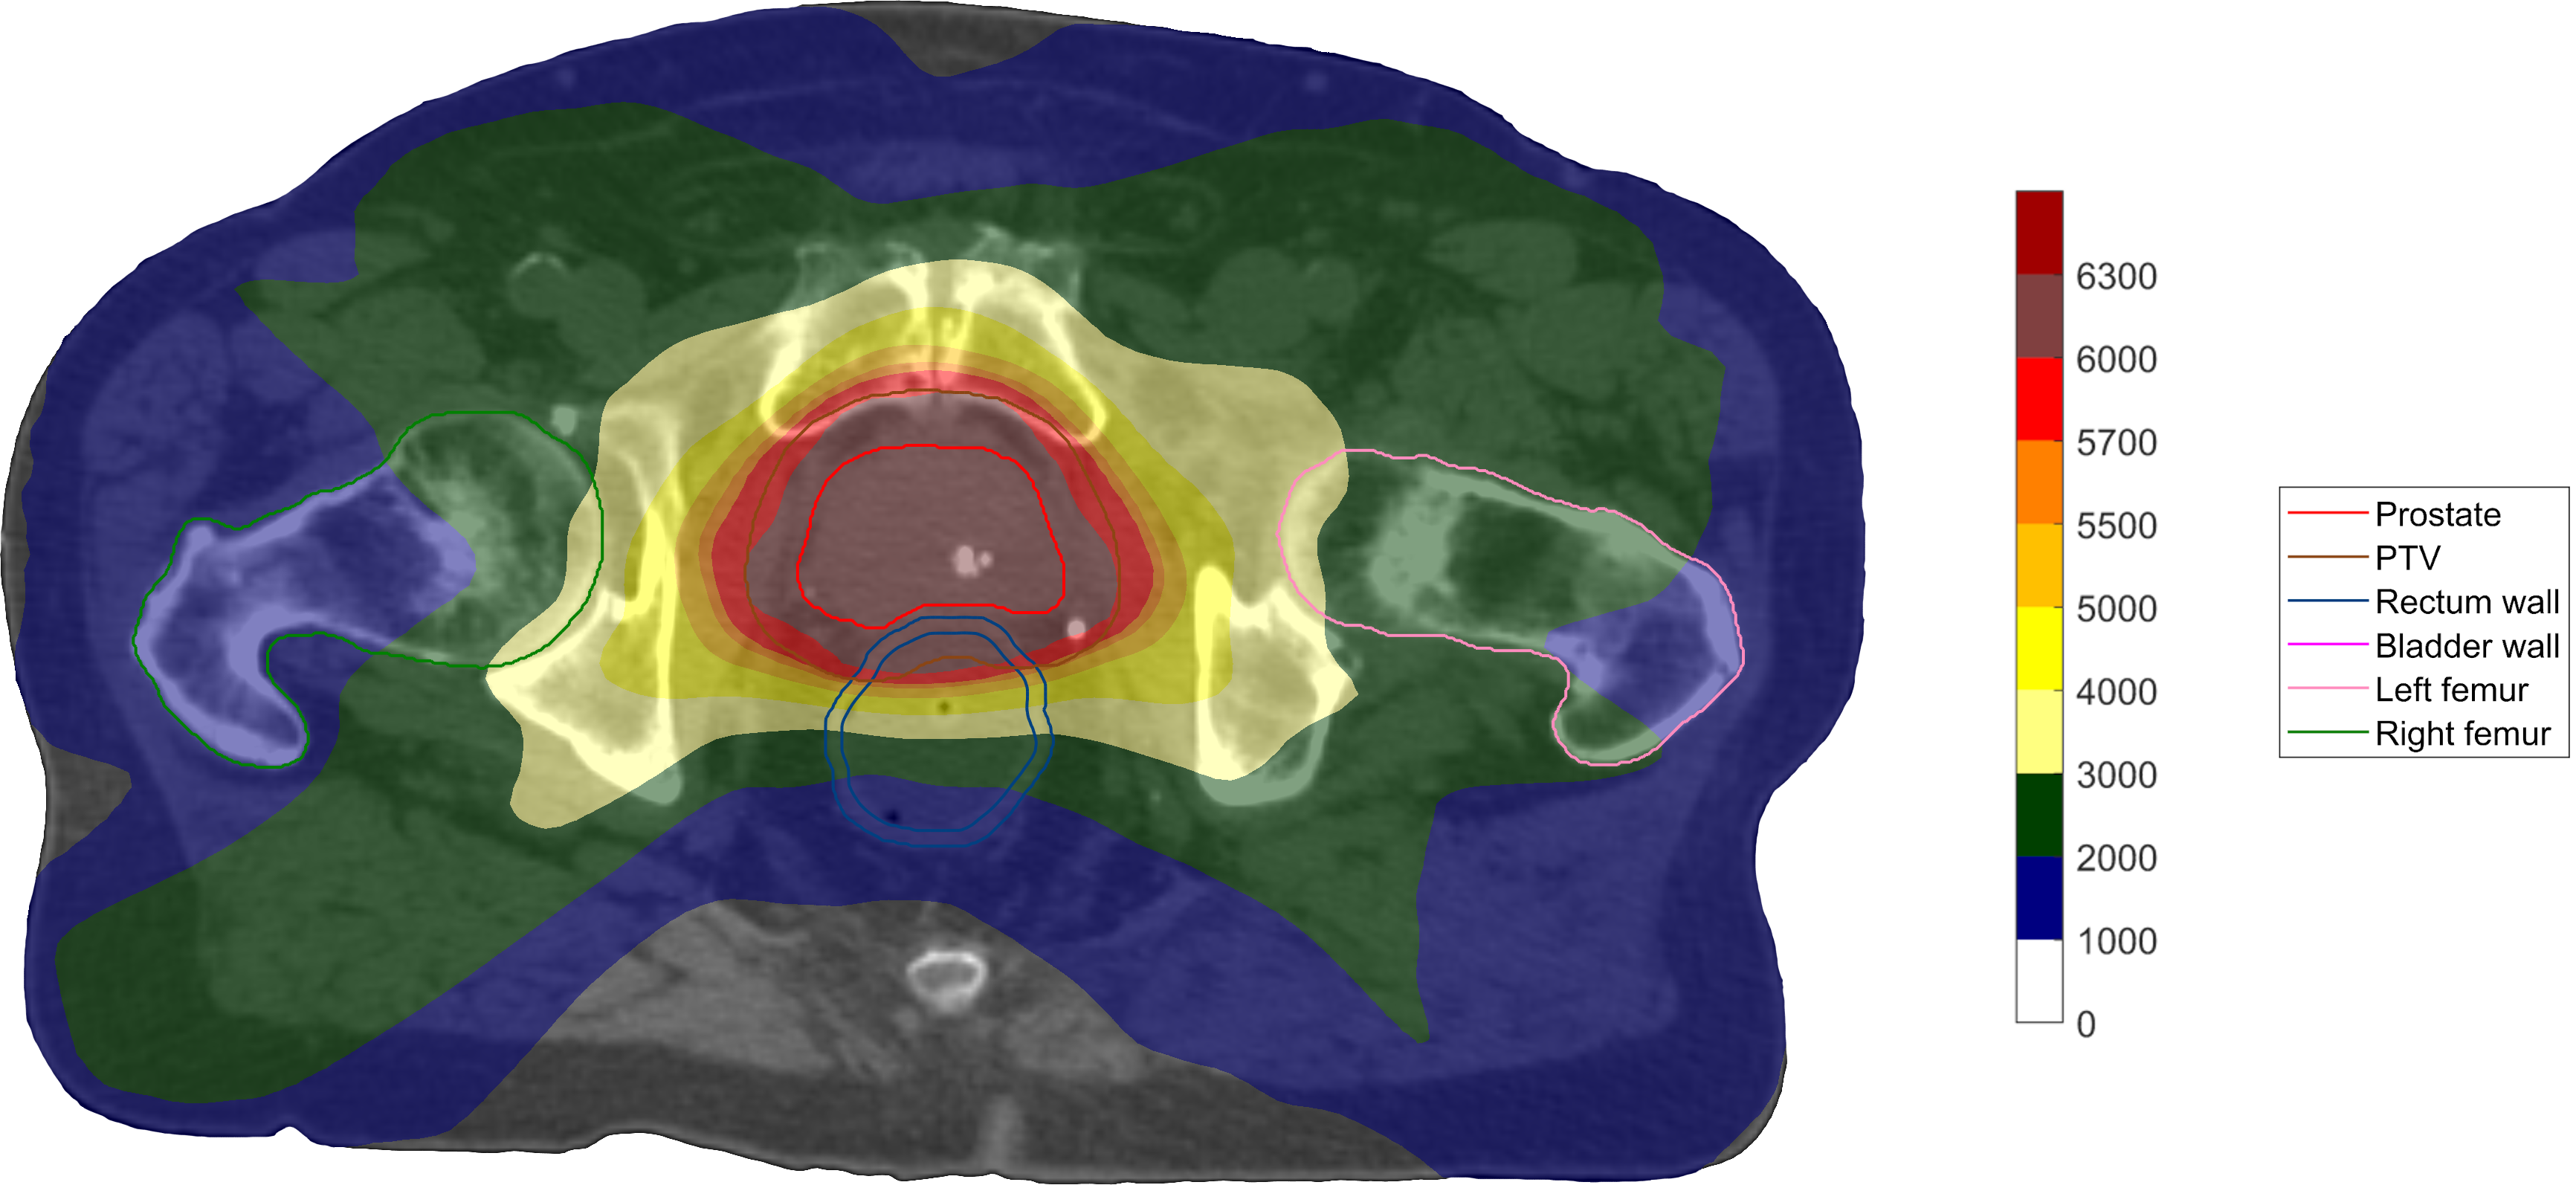

Figure 2 shows DVH comparisons between the formulations, and Figure 3 shows the spatial dose distributions. One can observe that the use of mean-tail-dose for the PTV tails leads to fewer extreme values in the lower tail, as can be expected from its properties—the D99.5%subscriptDpercent99.5\operatorname{D}_{99.5\,\%}D0.5%subscriptDpercent0.5\operatorname{D}_{0.5\,\%} range for the PTV was 5690cGy5690cGy5690\;\mathrm{cGy}6207cGy6207cGy6207\;\mathrm{cGy} for this case, compared to 5565cGy5565cGy5565\;\mathrm{cGy}6222cGy6222cGy6222\;\mathrm{cGy} for the case with only dose-at-volume and 5279cGy5279cGy5279\;\mathrm{cGy}6273cGy6273cGy6273\;\mathrm{cGy} for the conventional formulation. It is also possible to see the effect of the goals being made more restrictive when using the same reference volume level in the replacement. Moreover, the relatively large CI shortfall of the conventional plan can be seen by comparing its spatial dose distribution to those of the direct formulations, which actually optimized on the goal.

Figure 3: Transversal cuts of the spatial dose distributions of the optimized plans on the prostate case using the conventional formulation (a) and the direct formulations with (b) and without (c) replacement of certain dose–volume goals by mean-tail-dose.